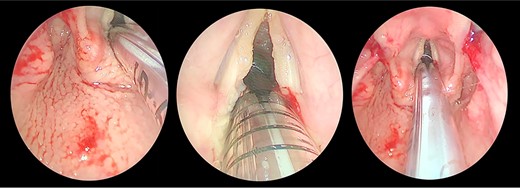

A contrasted neck CT scan showing bilateral asymmetric thickening of the vocal folds with medialization of the right vocal fold.

The patient maintained good oxygen saturation levels in room air with no signs of respiratory distress. She had a hoarse voice with a maximum phonation time of 10 s. Neck examination was unremarkable. Bedside transnasal flexible endoscope revealed bilateral vocal folds movement with polypoid lesions involving the middle two-thirds of the right vocal fold and the posterior part of the left vocal fold with edematous interarytenoid mucosa. Moreover, polypoid lesions were also seen in the base of tongue, epiglottis, with cobblestoning of the posterior pharyngeal wall (Figs 1 and 2). Basic laboratory tests were within the normal range. A contrasted neck computed tomography (CT) scan revealed bilateral asymmetric thickening of the vocal folds with medialization of the right vocal fold, with no enlarged cervical lymph nodes (Fig. 3).